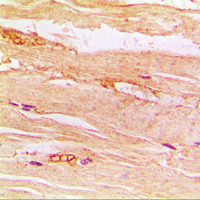

Intended Uses: This sandwich kit is for the accurate quantitative detection of Human Glucose transporter 4 (also known as GLUT4) in serum, plasma, cell culture supernates, Ascites, tissue homogenates or other biological fluids.

Principle of the Assay: This kit is an Enzyme-Linked Immunosorbent Assay (ELISA). The plate has been pre-coated with Human GLUT4 antibody. GLUT4 present in the sample is added and binds to antibodies coated on the wells. And then biotinylated Human GLUT4 Antibody is added and binds to GLUT4 in the sample. Then Streptavidin-HRP is added and binds to the Biotinylated GLUT4 antibody. After incubation unbound Streptavidin-HRP is washed away during a washing step. Substrate solution is then added and color develops in proportion to the amount of Human GLUT4. The reaction is terminated by addition of acidic stop solution and absorbance is measured at 450 nm.